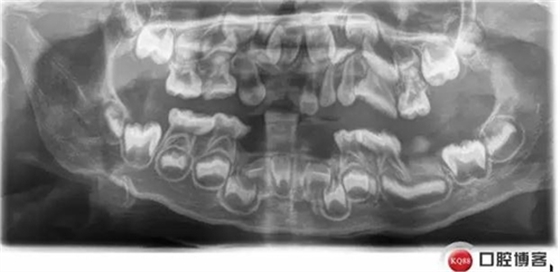

復(fù)診X線:

低磷脂酶癥是一種罕見的遺傳代謝異常,缺乏組織非特異性堿性磷酸酶活性,口腔表現(xiàn):牙齒萌出遲緩,乳恒牙均易早失,脫落牙齒的牙根長(zhǎng)度無變化。乳前牙最易受累而早失。病程中無明顯疼痛,牙周無明顯炎癥。X線片示牙釉質(zhì)正常,髓腔和和根管增大,牙槽骨有吸收。